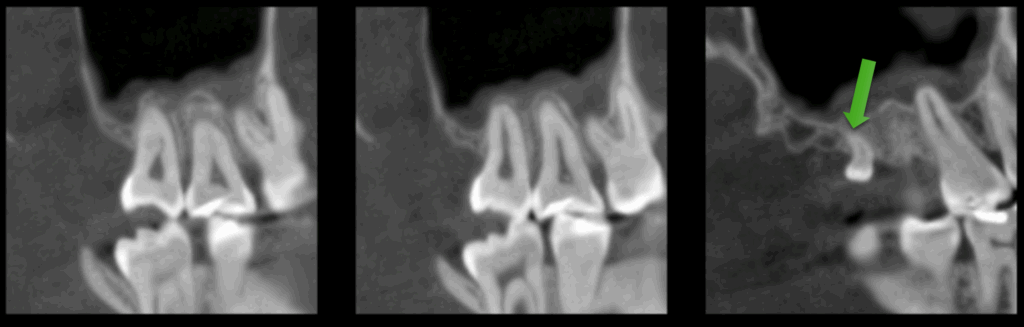

A la evaluación de la tomografía computarizada (en cortes axiales y transaxiales) se puede observar la presencia de una pieza supernumeraria de tamaño reducido (microdiente)localizada por lingual de la pieza 18 y que al evaluar los cortes tangenciales se aprecia una discreta dilaceración hacia distal.

Aunque muchos son asintomáticos y se detectan de manera incidental en estudios radiográficos, otros pueden interferir en la erupción normal o complicar procedimientos quirúrgicos. El diagnóstico preciso requiere radiografías panorámicas o, idealmente, tomografía computarizada de haz cónico (CBCT), que permite evaluar posición tridimensional y relación con estructuras vecinas.